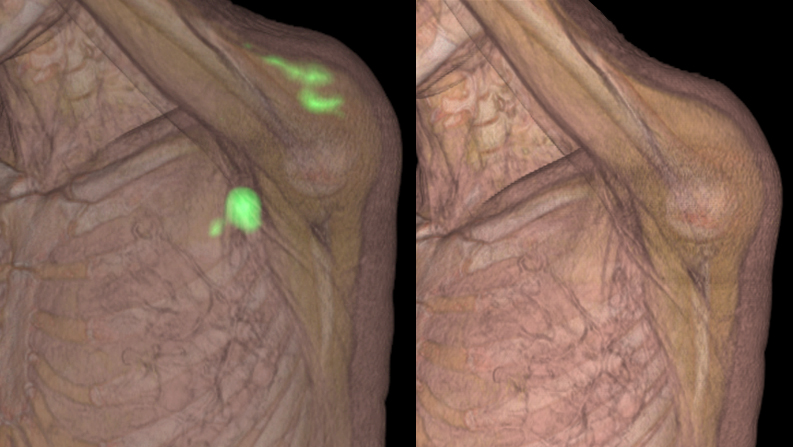

Según explica, las vacunas suponen la activación del sistema inmune, una hiperreactividad inmunológica que no pasa inadvertida en los estudios de imágenes PET-CT, que se hacen a los pacientes con cáncer en sus controles habituales. "Ya desde los primeros meses de aplicación de la campaña de vacunación pudimos ver en las imágenes PET el reflejo de la activación del sistema inmune", aclara Maldonado.

Recuerda igualmente que los pacientes vacunados muestran con mayor frecuencia dos tipos de reacciones: inflamación en la musculatura del lugar de inyección y la aparición de adenopatías locales, en especial en la axila del mismo lado de la inyección.

"Estas imágenes son la reacción normal del cuerpo a la aplicación de las vacunas y no indican malignidad. Es muy importante que tanto los oncólogos como los médicos nucleares conozcan este tipo de activaciones en los enfermos vacunados para que no sean tomadas por una recaída tumoral", subraya el especialista de Quirónsalud.